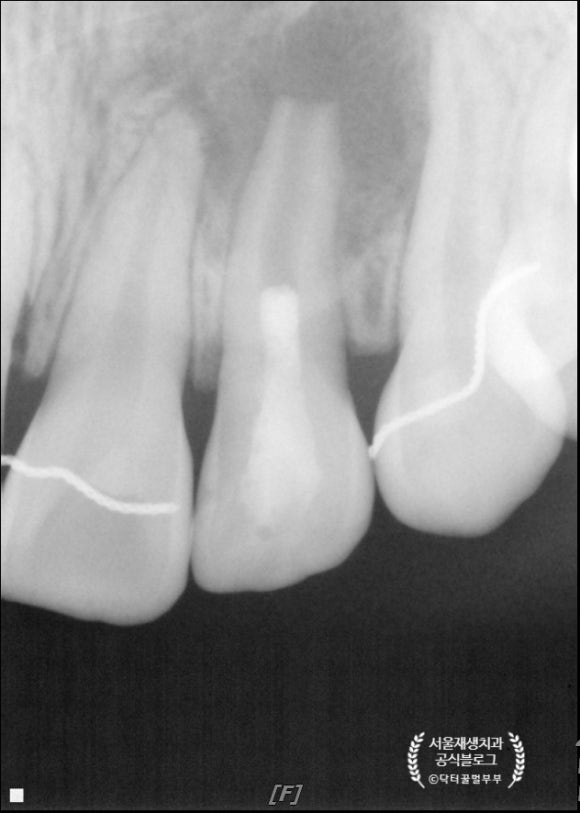

두 달 후에 왔습니다.

아직까진 그닥 달라진게 없어보이죠?

하지만 까만 동그라미(=치근단병소)의 가장자리를 보면

안개처럼 뿌옇게 신생골이 자라오는 것을 보실 수 있습니다.

보통 성인은 3개월 정도는 지나야 뼈의 재생이 관찰되는데,

역시 어린이는 회복이 빠릅니다^^